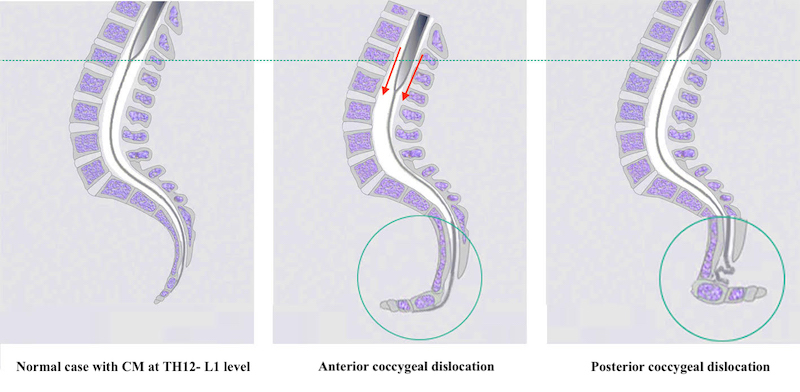

30/07/2019 Post-SFT The Filum disease and the Neuro-Cranio-Vertebral Syndrome: definition, clinical picture and imaging features.

The Filum disease and the Neuro-Cranio-Vertebral Syndrome: definition, clinical picture and imaging features.